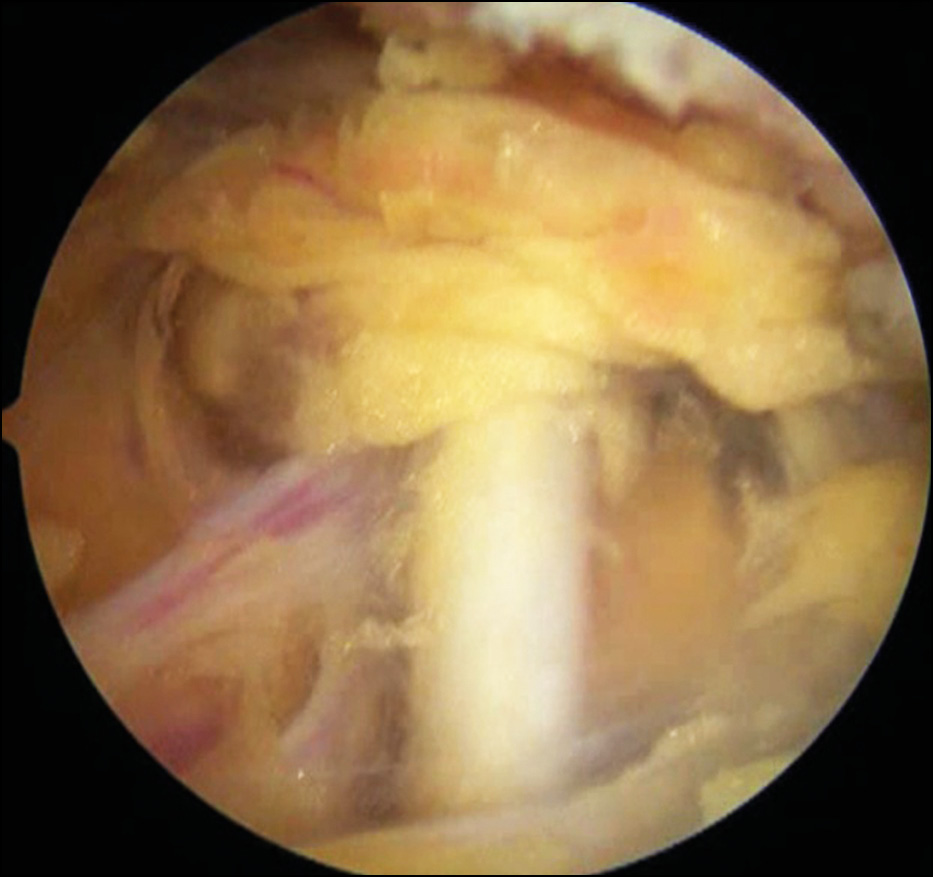

In Stage 2, the arthroscope was transferred to the anterior port, and the main nerves (n. axillaris and n. musculocutaneus) were visualized (Fig. 6). The area of damage to the articular surface of the scapula and the lower edge of the coracoid process were decorticated until pinpoint bleeding appeared (Fig. 7), thereby reducing the risk of bone autograft splitting during its collection, and increasing the contact area, congruence between the cavity of the scapula and the coracoid process (Fig. 8).

Fig. 6. Isolation of the axillary nerve (n. axillaris).